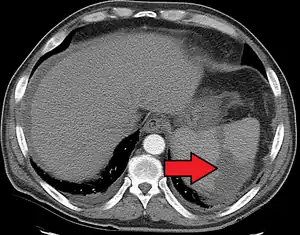

a, b) Splenic infarction.

Splenic infarct seen on CT

An abdominal CT scan is the most commonly used modality to confirm the diagnosis,[3] although abdominal ultrasound can also contribute.[16][17][18]